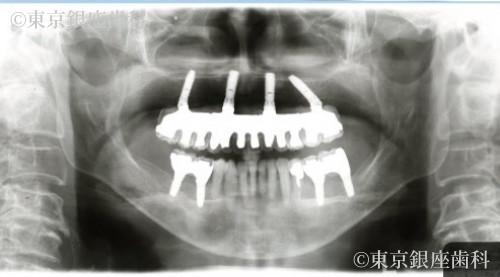

After

またインプラント埋入手術後当日に固定式の仮の人口歯を装着することをご希望されましたので、4本のインプラントを支えとし、全顎な固定式の人工歯を装着(ワンデイインプラント®)する計画をいたしました。

また下顎は奥歯に左右2本ずつのインプラントを支えとした4歯の人工歯を装着し機能回復を予定いたしました。

上顎に関して、ワンデイインプラントによって少ない本数のインプラントを支台とした全顎的な人工歯での機能回復が得られました。

噛み合わせや、整った歯の並びによりスムーズな咀嚼運動が可能となりました。

また下顎は奥歯だけのインプラント治療で安定した噛み合わせを得ることができました。